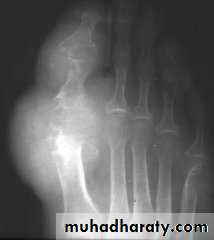

GOUT

• Heterogeneous group of entities characterized by recurrent attacks of arthritis secondary to deposition of sodium urate crystals in and around joints.• *90% of patients are male

• Radiographic features

• *Lower extremity > upper extremity; small joints > large joints

• * First MTP is most common site

• * Marginal, peri articular erosions: overhanging edge

• * Erosions may have sclerotic borders

• * Joint space is preserved

• * Soft tissue and bursa deposition

• Tophi: juxtaarticular, helix of ear

• * Tophi calcification, 50%